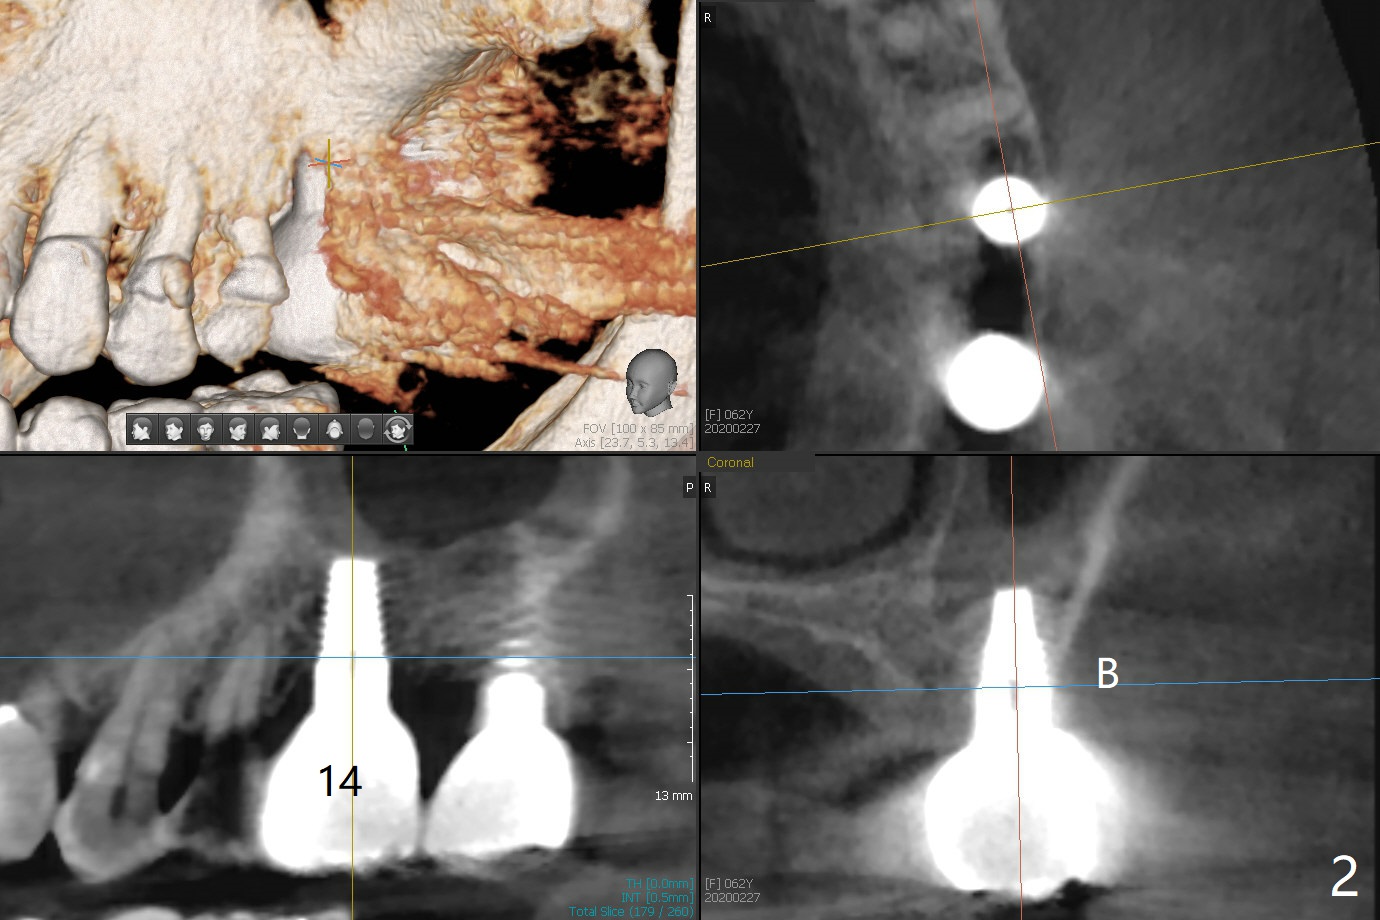

Since the bone density at #18 is low, under drilling is required (with guide). A 5x11 mm tissue-level implant will be inserted initially through the metal sleeve (Fig.3). Double check the trajectory in the second part of place-ment without the sleeve.